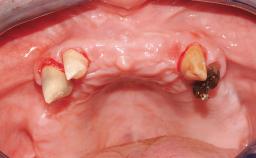

A 68-year-old, completely edentulous male patient presented for evaluation and treatment options. He reported excellent general health and was taking no regular medication. He had been edentulous for approximately 12 years, having lost his teeth to periodontal disease and dental caries. The patient’s chief complaint was incompetent function. His secondary concerns included his appearance and the desire for a predictable outcome. He attributed his reduced functional capacity to his lower complete denture, which he described as poor. He was particularly concerned with the denture’s instability and poor fit. In general terms, he was satisfied with the maxillary complete prosthesis. The maxillary prosthesis was characterized by adequate retention, stability, and support, although the fit was considered less than ideal.